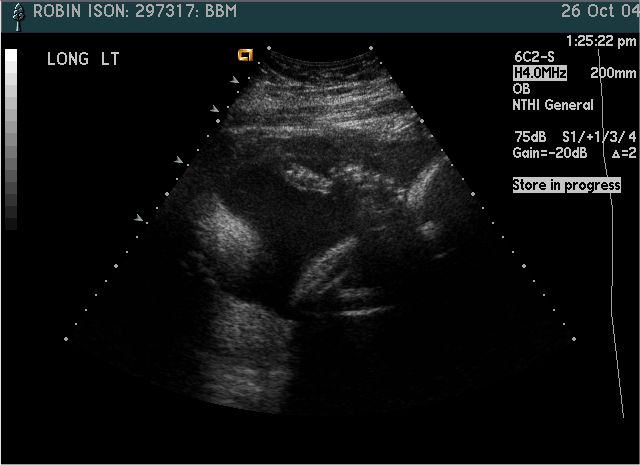

Pictures from Ultrasound at 30 weeks.